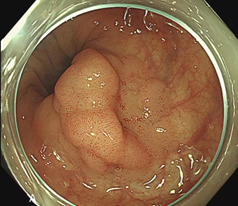

很多人在检查时发现有肠道息肉,一般医生会建议择机切掉,或者当时就顺便切掉,以绝后患。

所以检查中发现比较小的息肉(小于0.5cm的)可以顺便切除,并不会感觉到疼痛。

1、比较大的息肉,在无麻醉切除过程中也会产生牵拉疼,患者会不自觉地挪动身体,这样会影响肠镜医生对肠镜以及手术刀的把控;

3、有的息肉基底比较宽,盲目直接切除会有出血的风险;

5、息肉大于2cm的息肉,要排除有无癌变可能,有无往更深的肌肉层生长。

大肠息肉摘除术后很容易复发。大约有50%的大肠息肉患者在术后4年内出现了息肉复发。

因此如果肠镜检查发现有息肉,虽然予以切除术,患者千万莫大意,仍要定期复查,尤其是息肉数目较多、息肉大、腺瘤性息肉者更要复查。